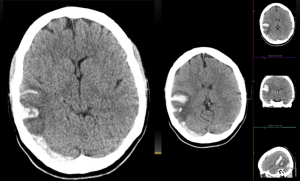

Varón, 73 años. En estudio de estenosis carotídea.